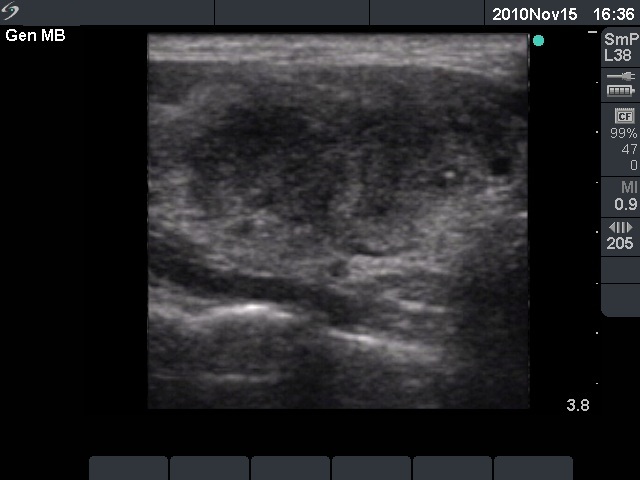

Initial examination (first row of images):

Ultrasonography: The right thyroid was echonormal and contained several small, insignificant lesions. There was a hypoechogenic lesion with blurred borders in the central and in the ventro-medial part of the left thyroid with increased intranodular blood flow.

The ultrasound pattern of de Quervain's thyroiditis and that of papillary cancer are very similar: a hypoechogenic lesion with blurred borders are found in both cases. They differ in vascularization statistically but the vascular pattern has only limited practical significance. In the acute phase of de Quervain's thyroiditis the vascularization is generally decreased but even in this case the situation was the opposite. The finding of not one but multiple hypoechogenic areas favored the possibility of subacute thyroiditis.